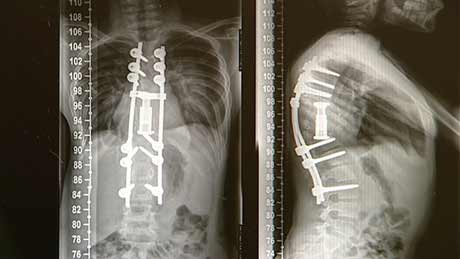

Christian Bach: Die Wirbelsäule des Mädchens war durch die Infektion völlig zerstört. Bei drei Operationen in Bulgarien wurde versucht, die betroffenen Wirbel zu entfernen. Doch es ist den Ärzten nicht gelungen, die Wirbelsäule zu stabilisieren. Über die Jahre ist es dadurch zu einem Buckel gekommen. Wir mussten das Mädchen von hinten aufschneiden. Dann mussten wir mehrere Rippen entfernen und die betroffenen Wirbelkörper rausnehmen. Dafür mussten wir die Wirbelsäule komplett durchtrennen. Nach dem musste die Wirbelsäule wieder gerade aufgerichtet werden mit Schrauben und Stäben.